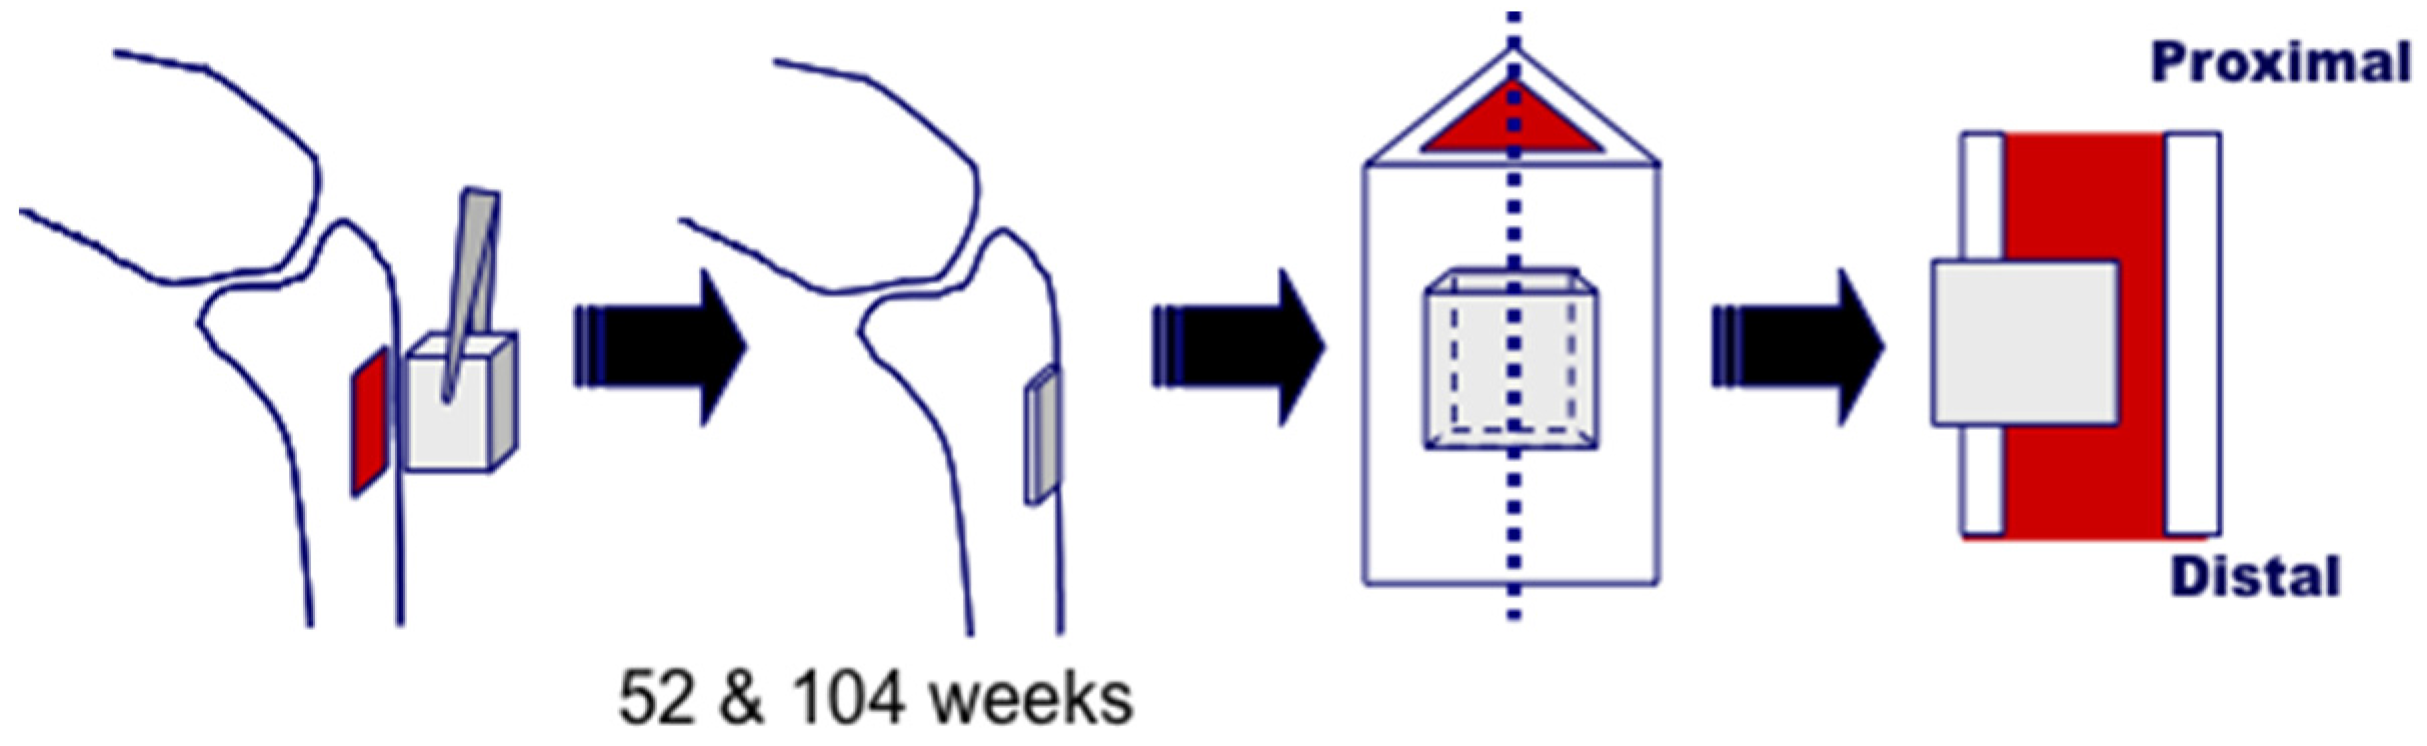

3.1. Bone Defect Animal Model

3.3. Bone Formation in Cortical and Medullary Bone Regions